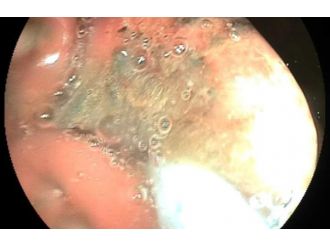

Mahkumun midesinden öyle bir şey çıktı ki!

Çöplükten öyle bir şey çıktı ki!